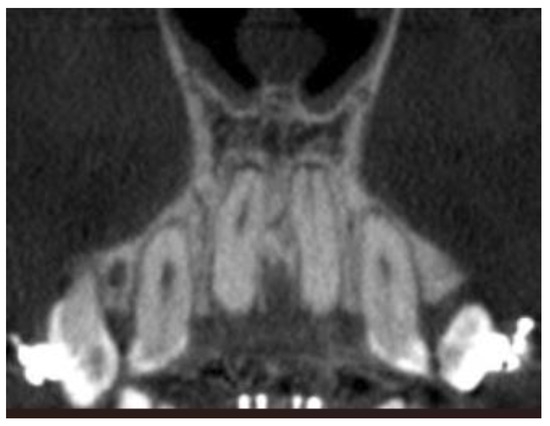

- Coronal plane:

- Angle formed by the long axes of the central incisors (values above zero for convergent roots, negative values for divergent roots).